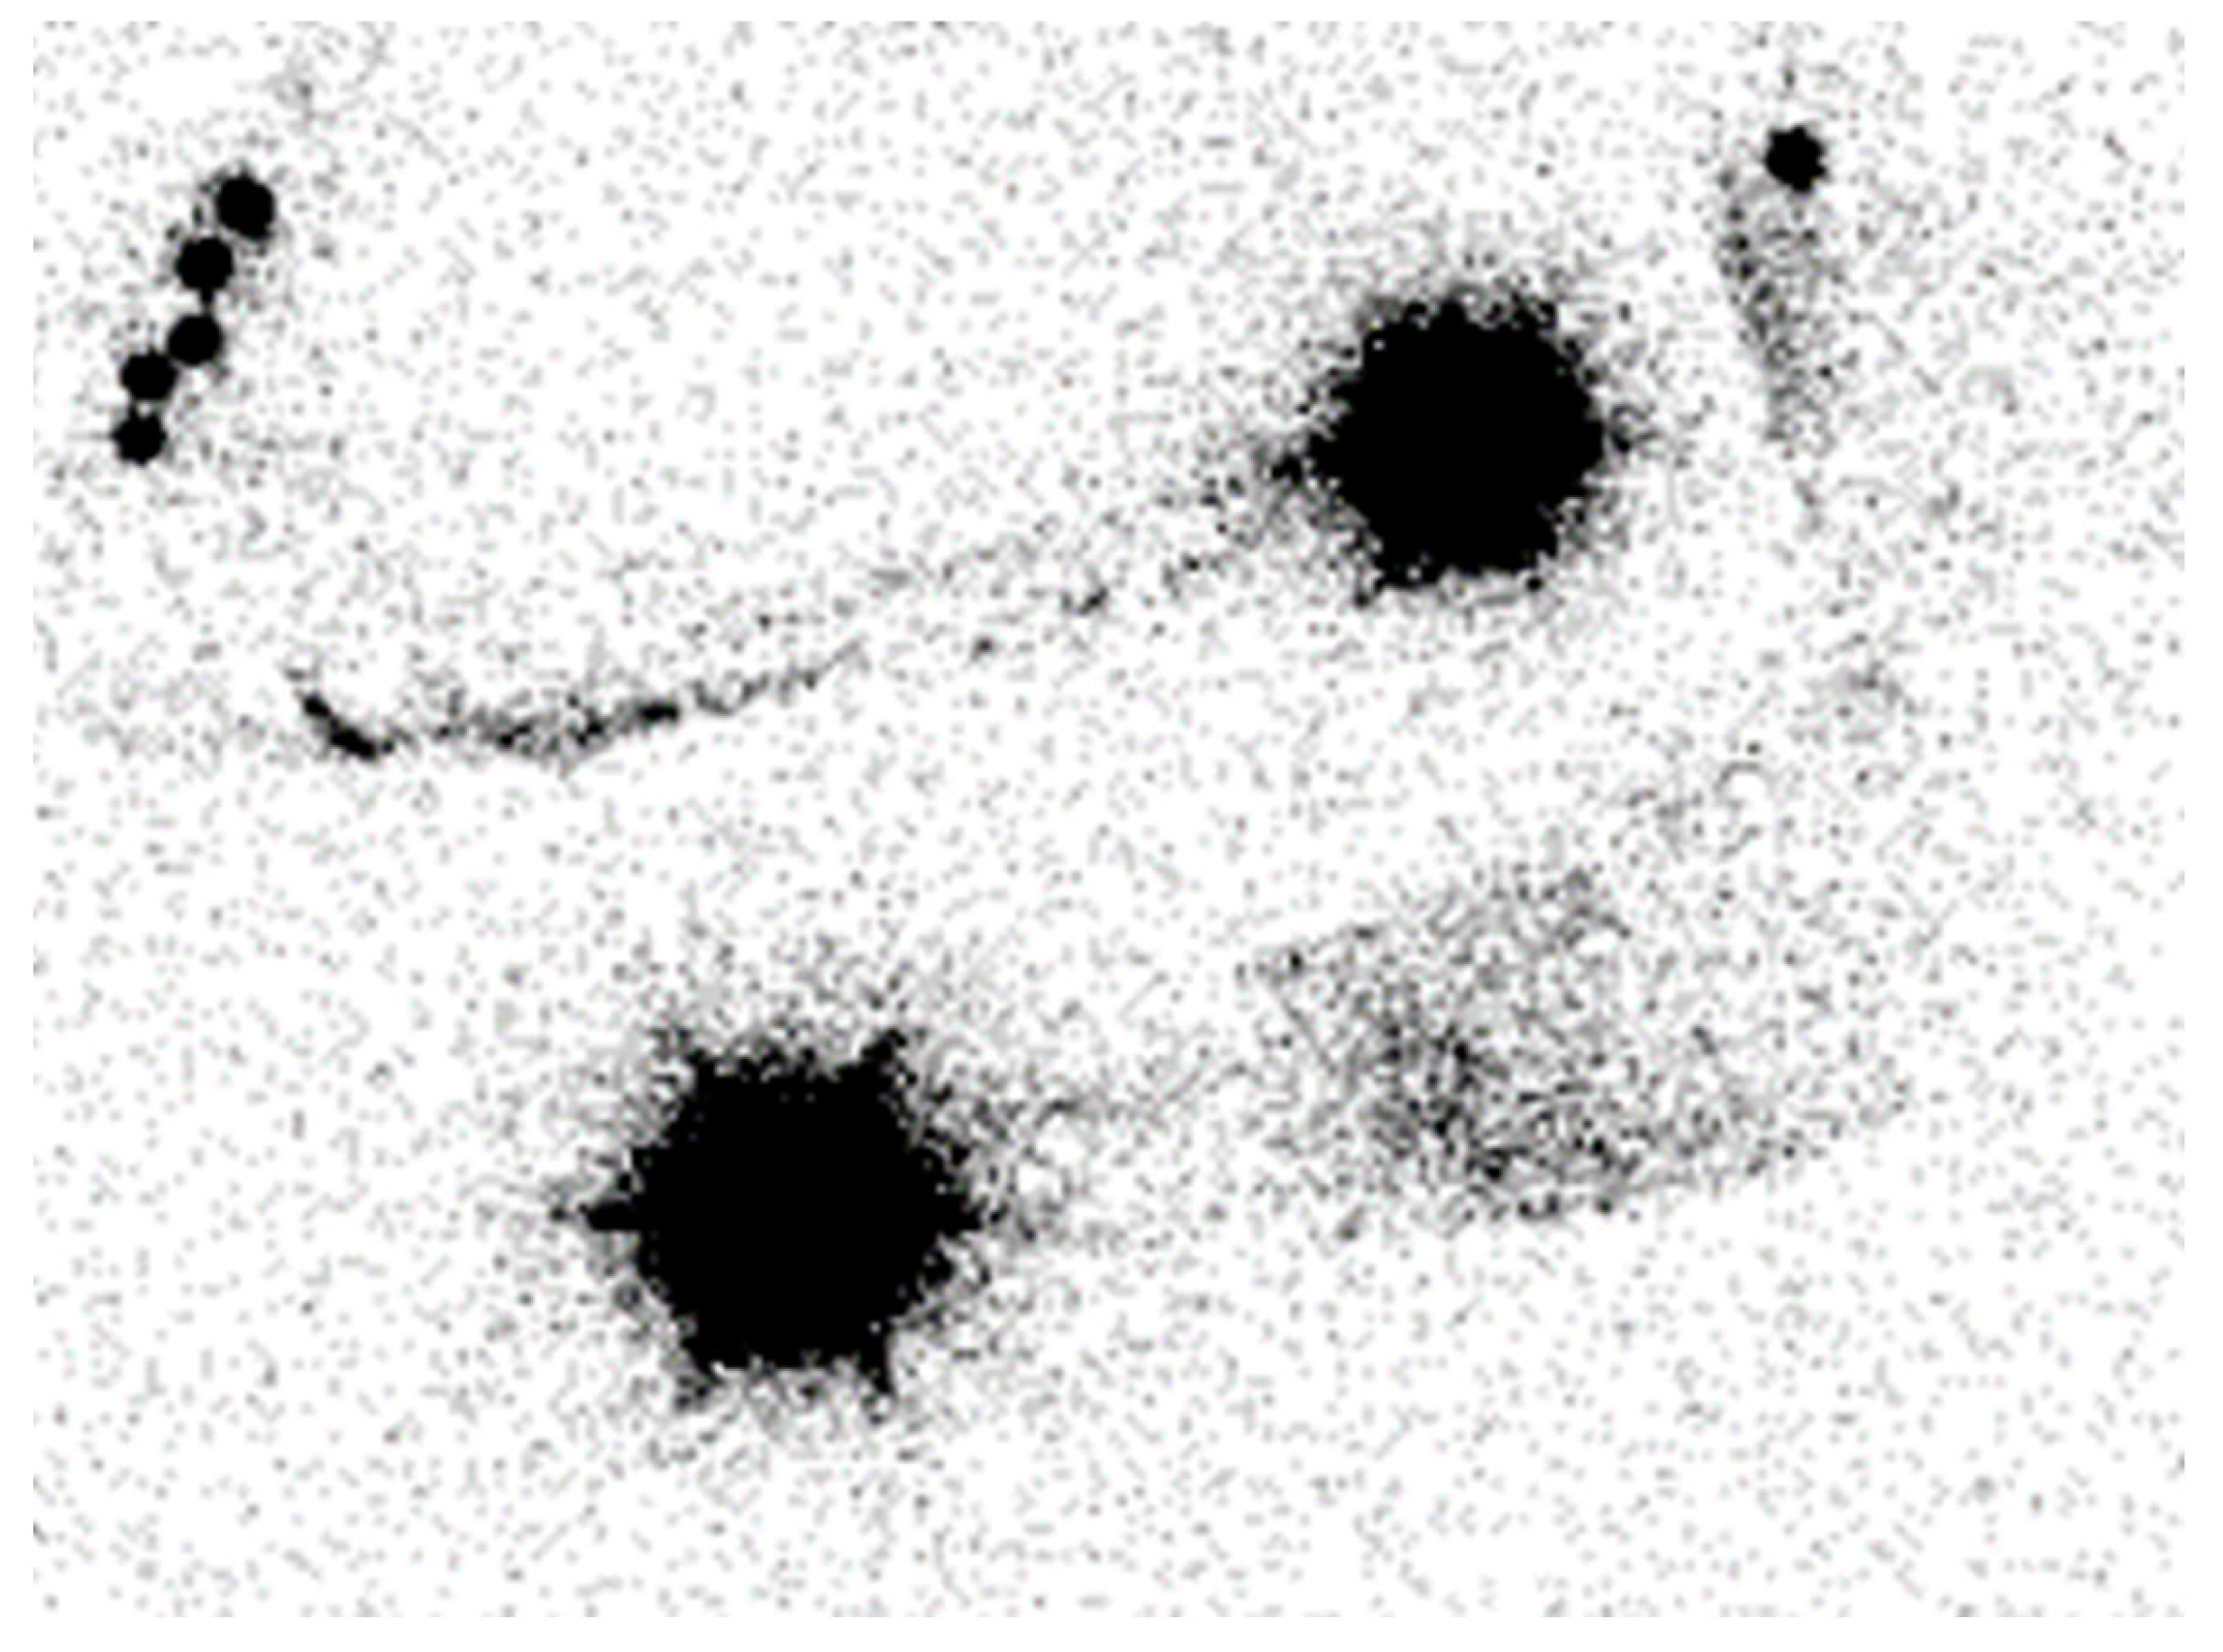

Figure 1.

Lymphoscintigraphy of the upper limb. It depicts severe left lymphedema.

Lymphoscintigraphy (LSG) gives a general overview of the lymphatic function and has been considered the gold standard for confirming lymphedema diagnosis [7]. This technique involves subdermally injecting a technetium-labeled colloid in the distal limb, followed by nuclear scanning to assess the lymphatic system. In patients with lymphedema, colloid transport through the lymphatics to the nodal basin is often compromised, resulting in delayed uptake and fluid leakage into the subcutaneous tissue [8]. Although LSG is helpful in evaluating central lymphatic system abnormalities and the extent of the disease, it has several limitations, including a poor anatomic/spatial resolution, the inability to assess interstitial tissues and accompany the vasculature of the lymphatic system, radiation exposure, and lengthy examination times [1,2,7] (Figure 1).